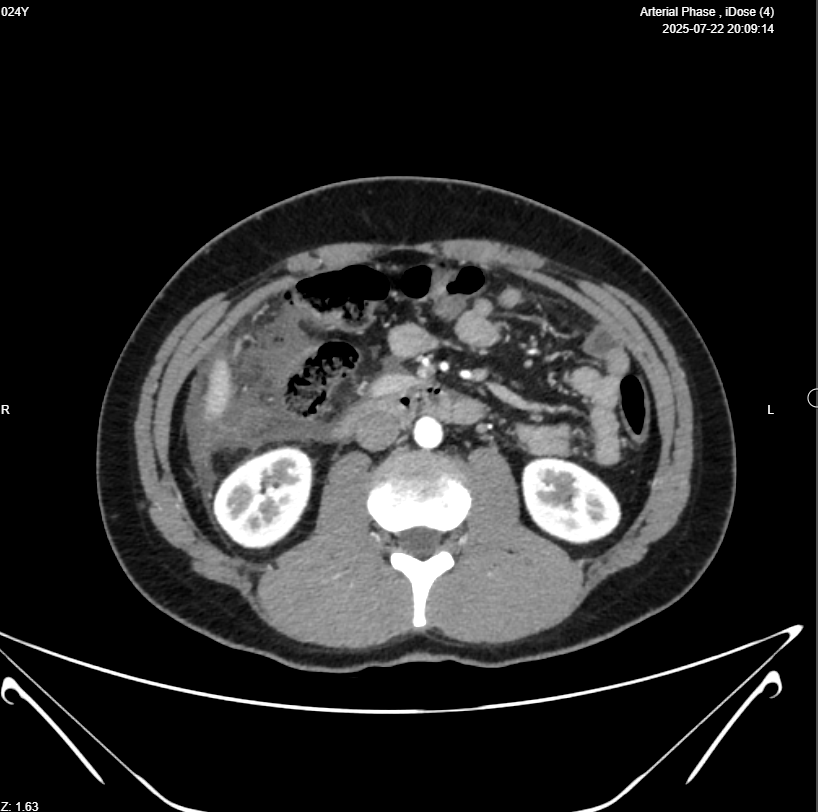

Right iliac fossa presence of Blind loop small bowel mass 39x16mm (Appendicitis ?) , associated with heterogenous mass 112x53mm , in the right sided sub-hepatic region, also associated with dilated bowel loop 26mm (ilieus?) & free intrabdominal fluid >100cc , picture mostly of ruptured viscus appendix ? with its sequel ?? , please for further study

Abdominal CT With IV Contrast

Clinical data: Appendicular mass.

- Evidence of 9 X 8 X 4cm Rt abdominal collection from Rt subhepatic region to RIF, contains fluid and gas, suggestive of an abscess, mostly from perforated appendix.

- Appendix shows diffuse wall thickening, diameter 11mm, with 2.5 X 2.5cm heterogeneously enhanced part in its tip which is in lower part of above mentioned collection, contains few calcifications, which raise suspicion of mucinous tumor.

- Marked inflammation in Rt subhepatic, paracolic gutter, which is surrounding cecum and ascending colon.

- Mild ascites.

- Several mesenteric LNs, mostly inflammatory.